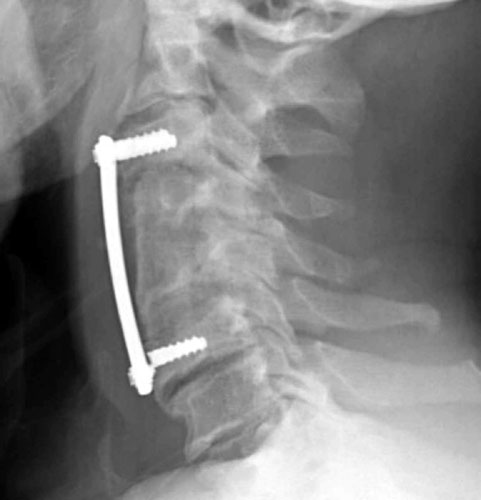

Lateral radiograph now 10 weeks post-operatively demonstrates interval fracturing of the two cortical screws in the vertebral body of C6. Superior displacement of the screws relative to the distal plate. Furthermore, the bone graft has tilted dorsally in its superior aspect as well.